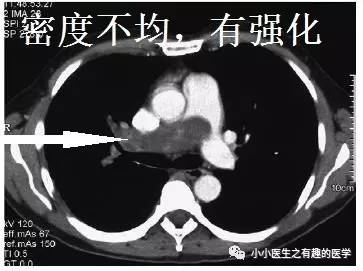

仔细看看,不对。

充盈缺损的地方,密度不均匀,并且,有强化,血栓里面没有血管,一般不会强化,所以,有可能是肿瘤。